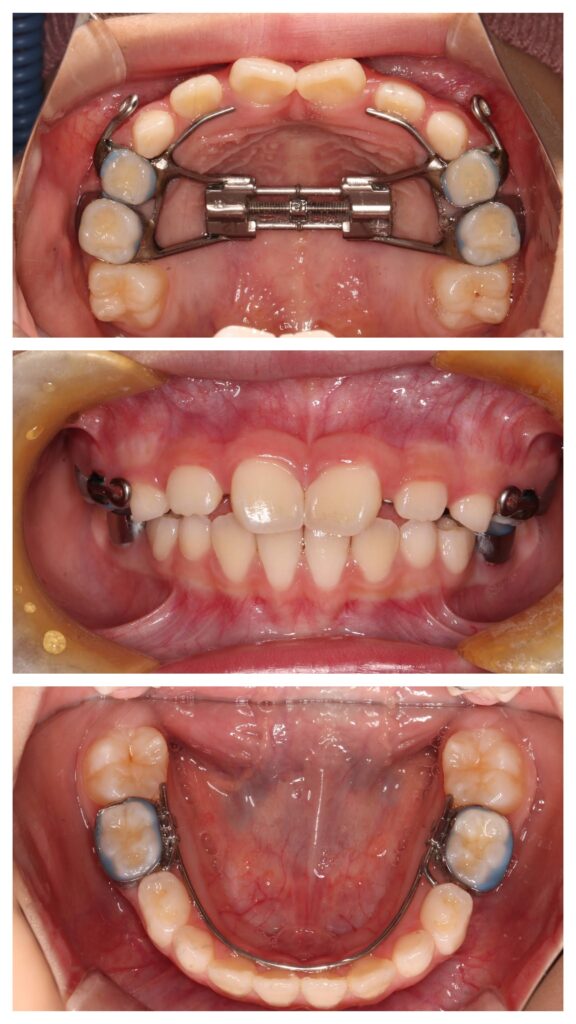

症例紹介①(顎顔面矯正)

今回の症例では、

成長期に上顎の拡大装置を使用。

BEFORE

歯列が狭く、前歯のスペース不足が認められました。

AFTER

歯列はU字型へ拡大。

永久歯が並ぶ余裕のあるアーチへ改善しました。